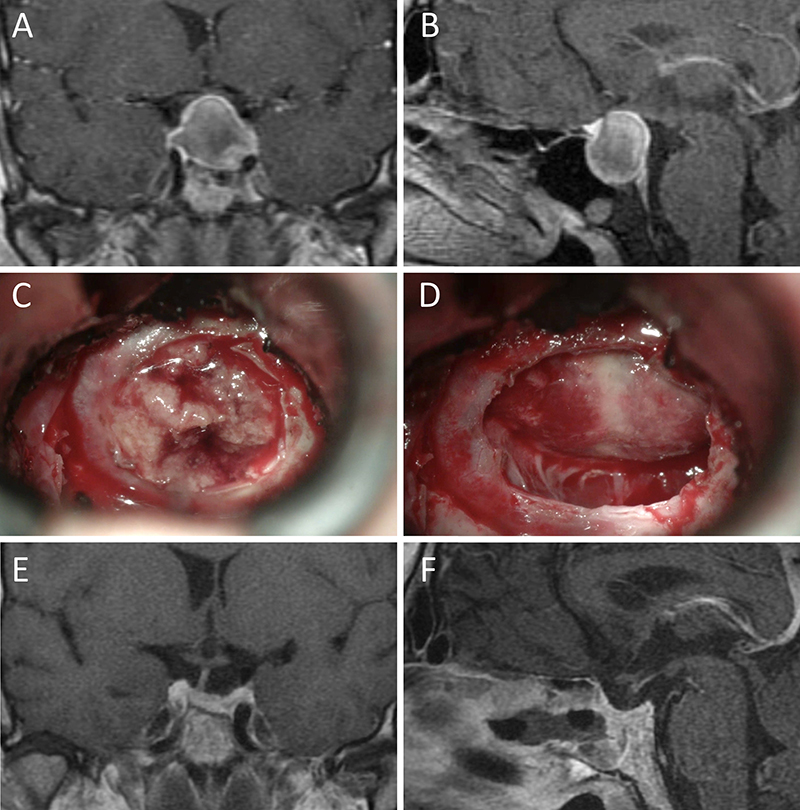

Presentamos 15 casos ilustrativos que consideramos representativos de nuestra serie: 4 enfermos con macroadenomas no funcionantes (figs. 1 a 4); 2 pacientes con macroadenomas con apoplejía (figs. 5 y 6); 4 enfermos con acromegalia (figs. 7 a 10); 3 pacientes con enfermedad de Cushing (figs. 11 a 13) y 2 enfermos con prolactinomas (figs. 14 y 15). El detalle de la presentación clínica de cada paciente y su correspondiente evolución postoperatoria se detalla en el epígrafe de cada ilustración.

Figura 2: Macroadenoma no funcionante en mujer de 31 años. La paciente presentó en el preoperatorio déficit visual que mejoró tras la cirugía. A-B: RM preoperatoria; C-D: intraoperatorio; E-F: RM postoperatoria.

Figura 3: Macroadenoma no funcionante en un hombre de 64 años. El paciente presentó en el preoperatorio déficit visual que mejoró tras la cirugía. A-B: RM preoperatoria; C-D: intraoperatorio; E-F: RM postoperatoria.